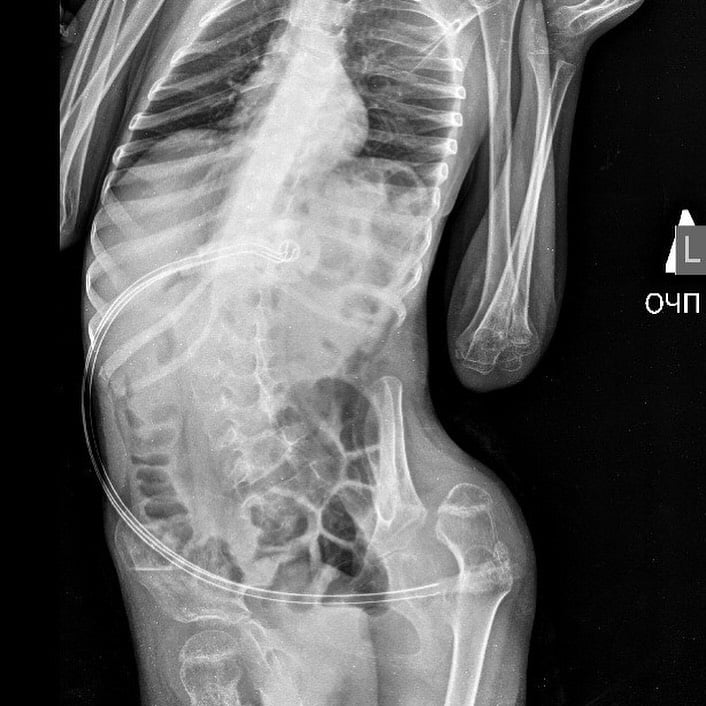

Як пояснив лікар у коментарі ZAXID.NET, 6-річний мешканець Рівненщини перехворів на аутоімунний енцефаліт, після чого втратив змогу самостійно їсти та пити. Нині вага хлопчика становить лише 12 кг, тому медики вирішили встановити ПЕГ-гастростому – спеціальну м’яку трубку, яка через невеликий прокол у шкірі вводиться безпосередньо до шлунка за допомогою гастроскопа.